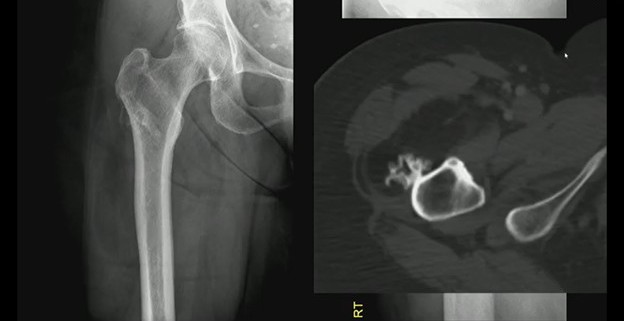

Imaging: Two views of an unusual surface lesion coming from the femur. Bone exostosis is evident. On the right, it doesn’t appear there’s any communication with the marrow space. Looking at soft tissues, you can make out a large, low-density mass—sort of draped below that little piece of bone coming off of the cortex.

CT shows the bone exostosis corresponds with this lesion coming from the surface of the cortex. It does *not* involve the medullary space; it doesn’t extend through the cortex. That low-density mass corresponds with this very fatty mass atop the bone.

Sure, there are a few septations, but no other suspicions.

DDX? This combination of a benign fatty mass attached to the underlying bone surface is a parosteal lipoma.

• “Trunk”—The bony outgrowth emerging from the femoral cortex.

• “Branches”—That large, low-density soft-tissue mass draped over the bone.

Bottom Line: Differentiating benign surface lesions from aggressive bone tumors is critical for avoiding unnecessary biopsies and patient anxiety. And if the “trunk” (i.e., bone) and “branches” (i.e., fat) are present sans marrow involvement, it’s likely just a lipoma.